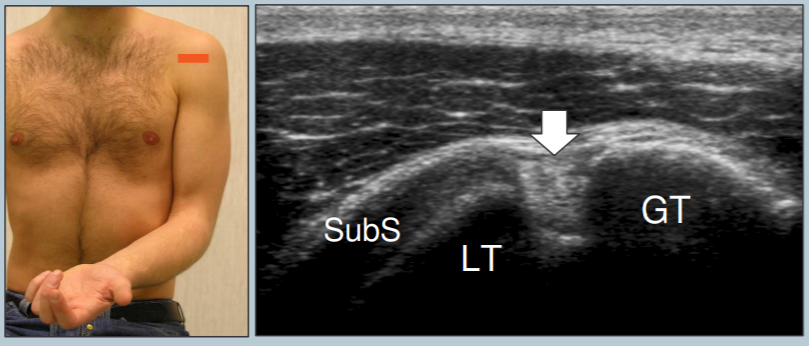

Long biceps

- Epaule en position neutre à 90° en supination

- Coupe axiale et longitudinale

- Incliner la sonde pour le suivre en axial dans sa partie supérieure quand il vire

- Tendon = Hyperéchoène et sujet à l’anisotropie (Change avec l’inclinaison de la sonde)

Entre la grande tubérosité (GT) et la petite (LT)

Sub-scapulaire

- Rotation externe de l’épaule, plaquée au corps

- S’insère sur le tubercule mineur

- Quelques fibres maintiennent le long biceps

- Identifier le processus coracoide

- Coupe axiale

- Manoeuvres dynamiques en axial (ouvrir et fermer l’épaule, regarder le comportement du tendon sous le coracoide

- Coupe longitudinale: on voit bien les espaces hypoechogènes entre les faisceaux du tendon